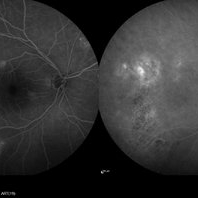

Central Serous Chorioretinopathy

Central Serous Chorioretinopathy

Jan 25 2022 by Olivia Rainey

Late phase widefield fluorescein angiography of a 60-year-old male with Central Serous Chorioretinopathy. Chronic history of CSR followed with observation without treatment prior to presenting at our office. The physician noted significant findings on exam and imaging with multifocal areas of inactive and active changes OD. FA shows superotemporal macular leakage, subtle inferonasal macular leakage and staining as well as multifocal hypercyanescence on ICG. Fortunately foveal sparing and thus observation is recommended at this time OD.

Photographer: Olivia Rainey, OCT-C, COA

Imaging device: Heidelberg Spectralis

Condition/keywords: 55-degrees, central serous chorioretinopathy (CSCR), central serous retinopathy (CSR), chronic central serous chorioretinopathy (CSCR), fluorescein angiogram (FA), fluorescein leakage, heidelberg spectralis, indocyanine green (ICG) angiography, late phase